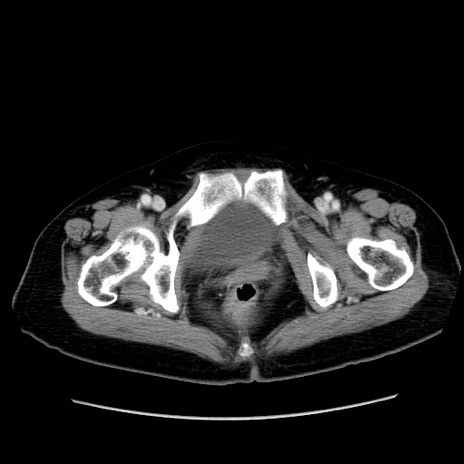

症例19(横断像)

【症例】80歳代女性

【主訴】下腹部痛

【現病歴】約8時間前より下腹部痛の出現あり、救急外来受診。

【既往歴】両側付属器切除

【身体所見】意識清明、下腹部正中に手術痕あり、その部位に一致して圧痛と反跳痛あり。腸蠕動音は亢進。

【データ】WBC 9300、CRP 0.15